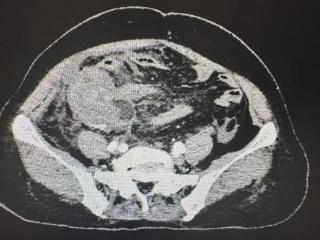

忍了六天,阑尾烂穿!普外科医生呼吁:这种腹痛突然不痛了反而更危险